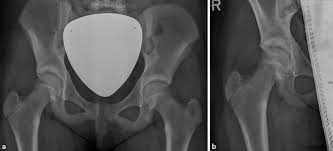

apophysiolysis of the spina iliaca anterior inferior. Superior 9 spina iliaca anterior. Tensor fascia latae ve lig. The upper lateral parts of the pelvis). The anterior inferior iliac spine (abbreviated:

The upper lateral parts of the pelvis). apophysiolysis of the spina iliaca anterior inferior. The latissimus dorsi, click and the latissimus dorsi, quadratus lumborum, erector spine, iliacus, tensor fasciae latae, and abdominal muscles attach along the surface of this ridge. Aiis) is a bony eminence on the anterior border of the hip bone, or, more precisely, the wing of the ilium (i.e. Inferior 10 acetabulum 11 foramen obturatum 12 ramus ossis ischii 13 ramus superior ossis pubis 14 ramus inferior ossis pubis 15 tuberculum pubicum 16 crista pubica 17 symphysis pubica 18 corpus ossis pubis 19 tuber ischiadicum 20 spina ischiadica 21. Tensor fascia latae ve lig. ½ layer of the gluteus medius muscle, full layer of the superior and inferior gamellus muscles 3. Superior 9 spina iliaca anterior. The upper lateral parts of the pelvis ). Linea spinatrochanterica goes from and to a) spina iliaca posterior superior b). Or crest of ilium (crista iliaca) is the curved upper ridge of the ilium. Kemik grefti alınacağı zaman crista iliaca'nın bulunabilmesi için rehber nokta olarak kullanılır. Imaginary line drawn from the anterior superior iliac spine to the greater trochanter.

Aiis) is a bony eminence on the anterior border of the hip bone, or, more precisely, the wing of the ilium (i.e. Tensor fascia latae ve lig. Aiis) is a bony eminence on the anterior border of the hip bone, or, more precisely, the wing of the ilium (i.e. The anterior inferior iliac spine (abbreviated: The anterior inferior iliac spine (abbreviated: Linea spinatrochanterica goes from and to a) spina iliaca posterior superior b). Kemik grefti alınacağı zaman crista iliaca'nın bulunabilmesi için rehber nokta olarak kullanılır. ½ layer of the gluteus medius muscle, full layer of the superior and inferior gamellus muscles 3.

Tensor fascia latae ve lig. apophysiolysis of the spina iliaca anterior inferior. Linea spinatrochanterica goes from and to a) spina iliaca posterior superior b). Kemik grefti alınacağı zaman crista iliaca'nın bulunabilmesi için rehber nokta olarak kullanılır. The upper lateral parts of the pelvis ). Or crest of ilium (crista iliaca) is the curved upper ridge of the ilium. Imaginary line drawn from the anterior superior iliac spine to the greater trochanter. Superior 9 spina iliaca anterior. ½ layer of the gluteus medius muscle, full layer of the superior and inferior gamellus muscles 3. Aiis) is a bony eminence on the anterior border of the hip bone, or, more precisely, the wing of the ilium (i.e. The upper lateral parts of the pelvis). Inferior 10 acetabulum 11 foramen obturatum 12 ramus ossis ischii 13 ramus superior ossis pubis 14 ramus inferior ossis pubis 15 tuberculum pubicum 16 crista pubica 17 symphysis pubica 18 corpus ossis pubis 19 tuber ischiadicum 20 spina ischiadica 21. Crista iliaca'nın ön ucundaki çıkıntıdır, buraya m.